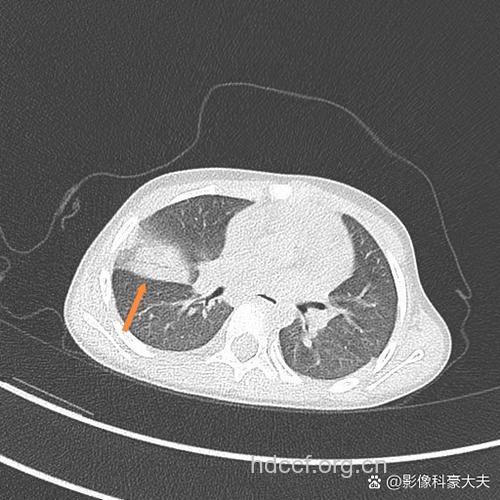

CT是有辐射的,一般不会轻易的给宝宝做,但是对于宝宝病情不能通过听诊器及血液检查得出的结果,就只能用CT来确诊了,通过CT可以很清楚的看到宝宝的肺部是否有阴影从而才能判定宝宝是否是肺炎。CT只要不是老做,偶尔做一次,是不会给宝宝造成太大影响的。